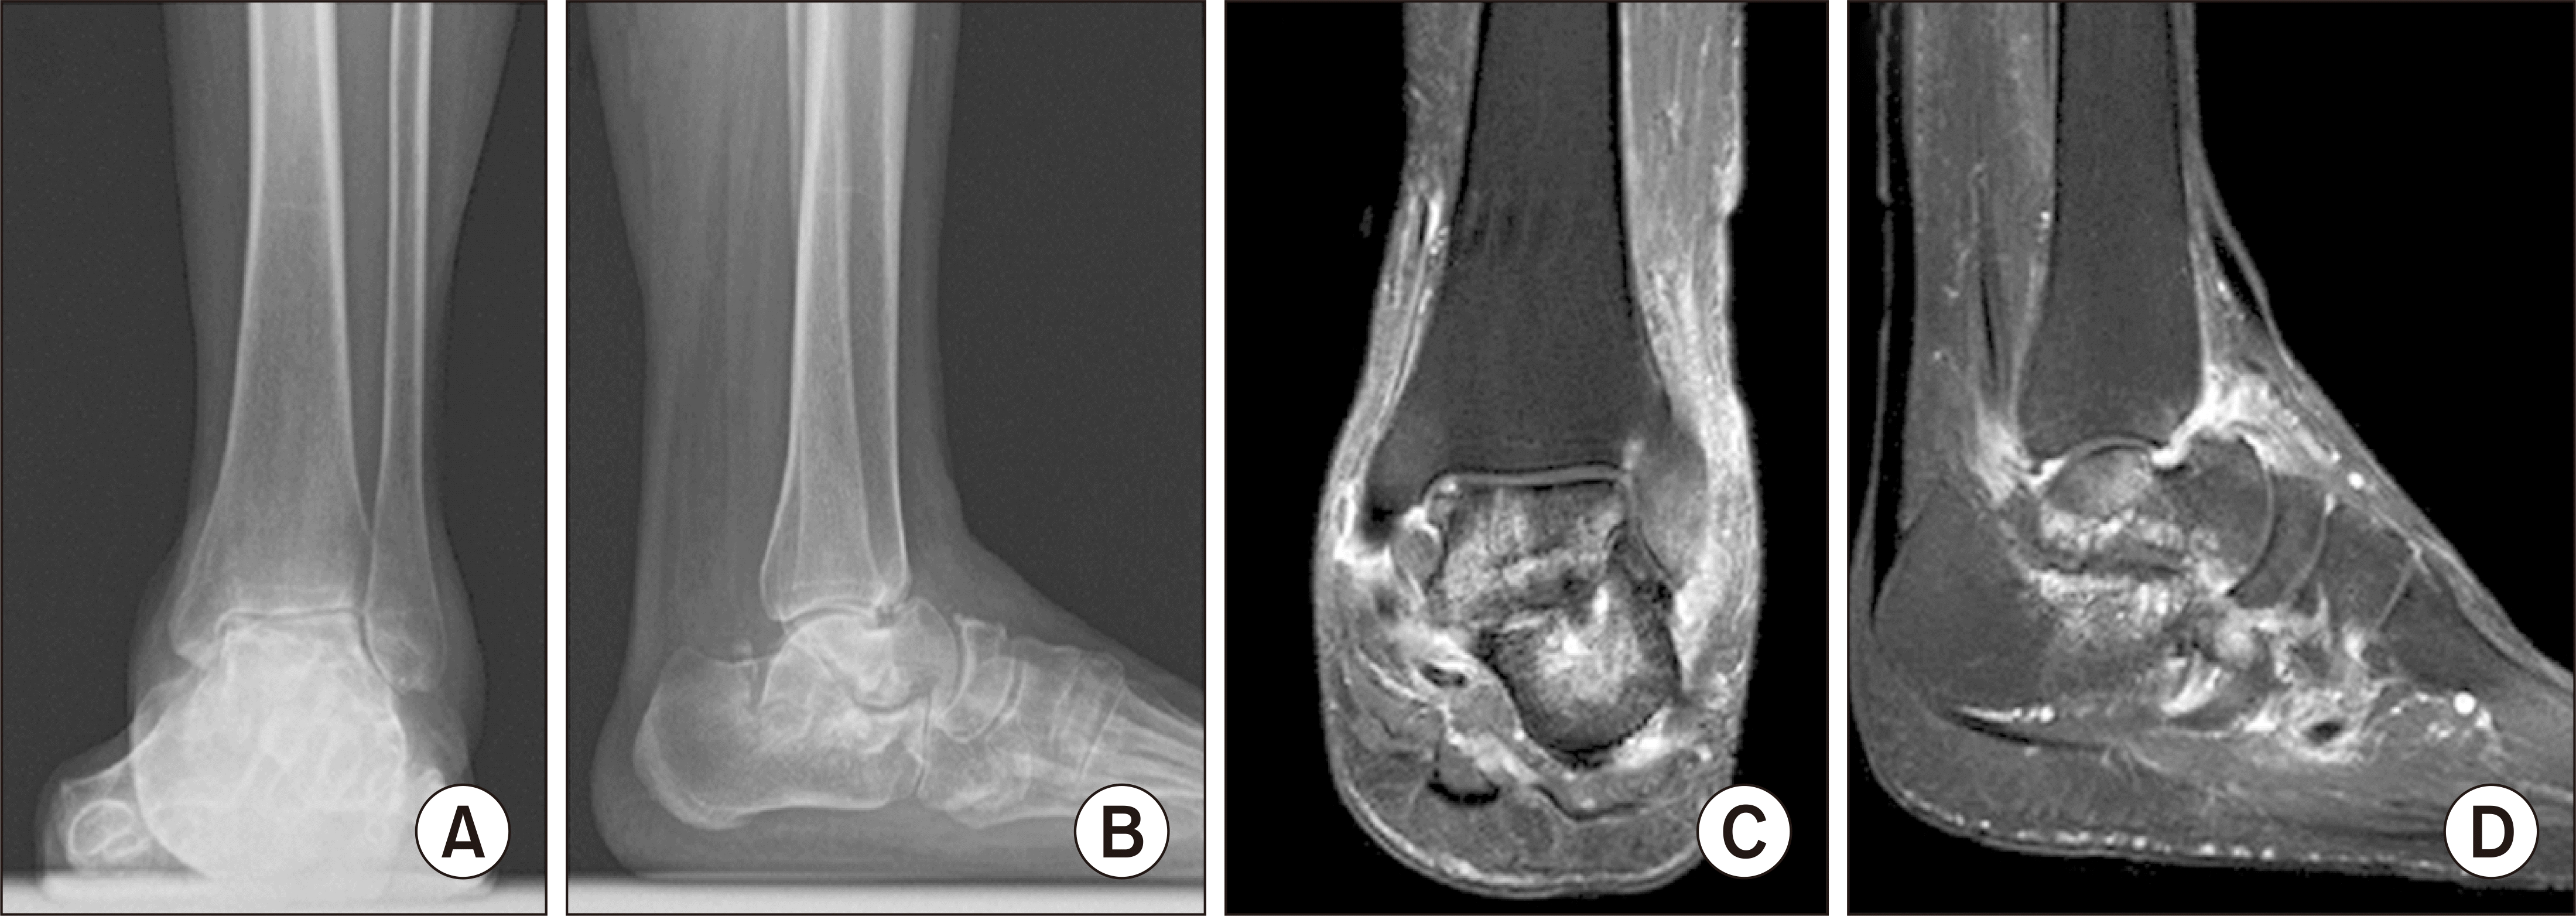

66세 여자 환자가 약 10년 전부터 특이 외상력 없이 발생한 좌측 족관절의 통증 및 부종을 주소로 내원하였다. 환자는 약 50년 전의 결핵 외의 특이 과거력은 없었다. 환자는 내원 5년 전부터 수년간에 걸쳐 좌측 족관절에 금침을 맞은 이력이 있었으나 음주, 흡연력은 없었고 스테로이드 치료를 받은 적은 없었다. 환자는 내원 1년 전부터 서서히 증상이 악화되었고, 내원 당시 시행한 이학적 검사에서 좌측 족관절의 전반적인 압통 및 경도의 부종이 있었다. 혈액 검사상 백혈구 수 4,000개/mm3, 적혈구 침강 속도 21 mm/hr, C-반응 단백 0.2 mg/dL의 정상 소견을 보였고 초음파를 이용한 족관절의 관절액 검사에서도 특이 소견이 없었으며 균 배양 검사는 음성 결과가 나왔다. 기립 발목 radiograph에서 거골의 침강 및 거골하 관절염 소견을 보였으며 자기공명영상(magnetic resonance imaging)에서 관절 부종을 동반한 좌측 거골 및 종골의 진행된 골파괴 소견이 관찰되어(Fig. 1), 거골의 골괴사 진단 하에 동종 거골을 이용한 경거종골 유합술을 계획하였다.

Figure 1

Preoperative simple ankle radiographs (A, B) and magnetic resonance imaging images (C, D) showing collapse of subtalar joint with bone destruction of talus and calcaneus.